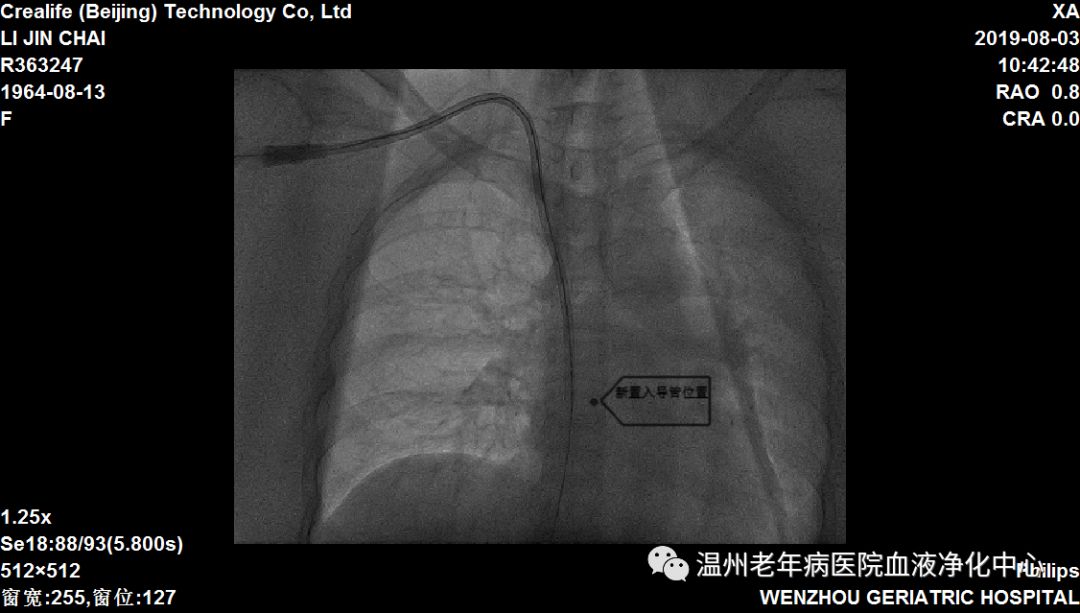

患者李某某,原发病为糖尿病肾病,罹患尿毒症13年,通路为右侧颈内静脉透析导管,患者双上肢静脉纤细,经评估不能建立自体动静脉内瘘及移植物血管内瘘,故保留导管透析已13年。近日,发现患者导管破损,出血、感染风险大,我院血液净化室主任林向东、卢寿荣医师等讨论后决定予DSA下更换导管。因患者置管时间久,考虑存在上腔静脉狭窄,常规更换导管操作可能出现拔管后无法重新置入导管,以及盲穿带来的血管破裂出血的风险,而选择DSA下能直观观察到狭窄严重程度,精确引导操作,增加手术成功率,提高手术安全性,遂决定于DSA下行中心静脉造影+球囊扩张术+更换导管术,经过大家细致操作,圆满完成手术。术毕患者导管动静脉端抽吸血流通畅,并顺利完成透析。

(新置入导管位置)